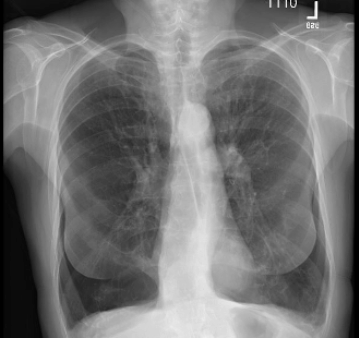

76 y/o male with homogenous emphysema and multiple comorbidities came off oxygen after treatment (Result not typical)

Successful atelectasis of the right middle lobe with 80% fissure completeness score